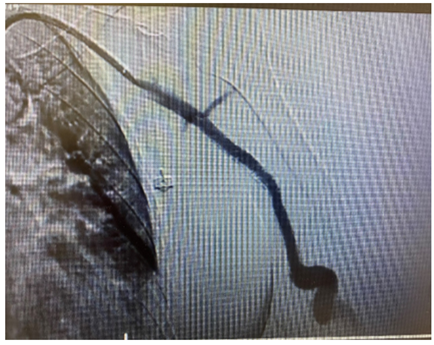

The patient was urgently submitted to an endovascular treatment of the AVF and brachial artery acute thrombosis. Under general anesthesia, a left common femoral artery was retrograde punctured guided with a duplex ultrasound to perform the whole intervention percutaneously with a proper sheat. Then, upper left arm arteriography showed: brachial artery occlusion immediately before stenting, with brachial artery refilling before anastomosis focal venous stenoses. (Figures 1 and 2).

Figure 2: Intraoperative image showing Indigo System thrombectomy.